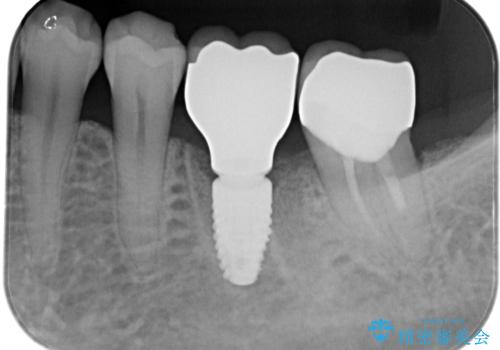

インプラント治療を希望されたため、インプラントを埋入し咬合機能を回復していきます。

骨の量は十分あったため、比較的短期間で治療は終了しました。

安定した咬み合わせとなり、痛みもなく安心して噛めるようになりました。